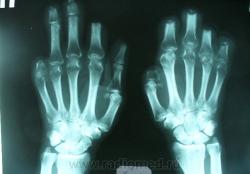

Пациент отпраздновал Рождество и прикорнул на свежем воздухе. В результате - ампутация пальцев рук и ног. Первый снимок сделан в ближайшие дни после операции. До сих пор п/опер. раны на пальцах рук не эпителизировались. Вчера проведено контрольное исследование. Ваше мнение, уважаемые коллеги, что это, недостаточный уровень ампутации? Остеомиелит? И то и другое?

А остеомиелит помоему есть.

При осмотре в ранах 3-4 пальцев правой кости и 3 и 5 п-в левой мелкие костные фрагменты.